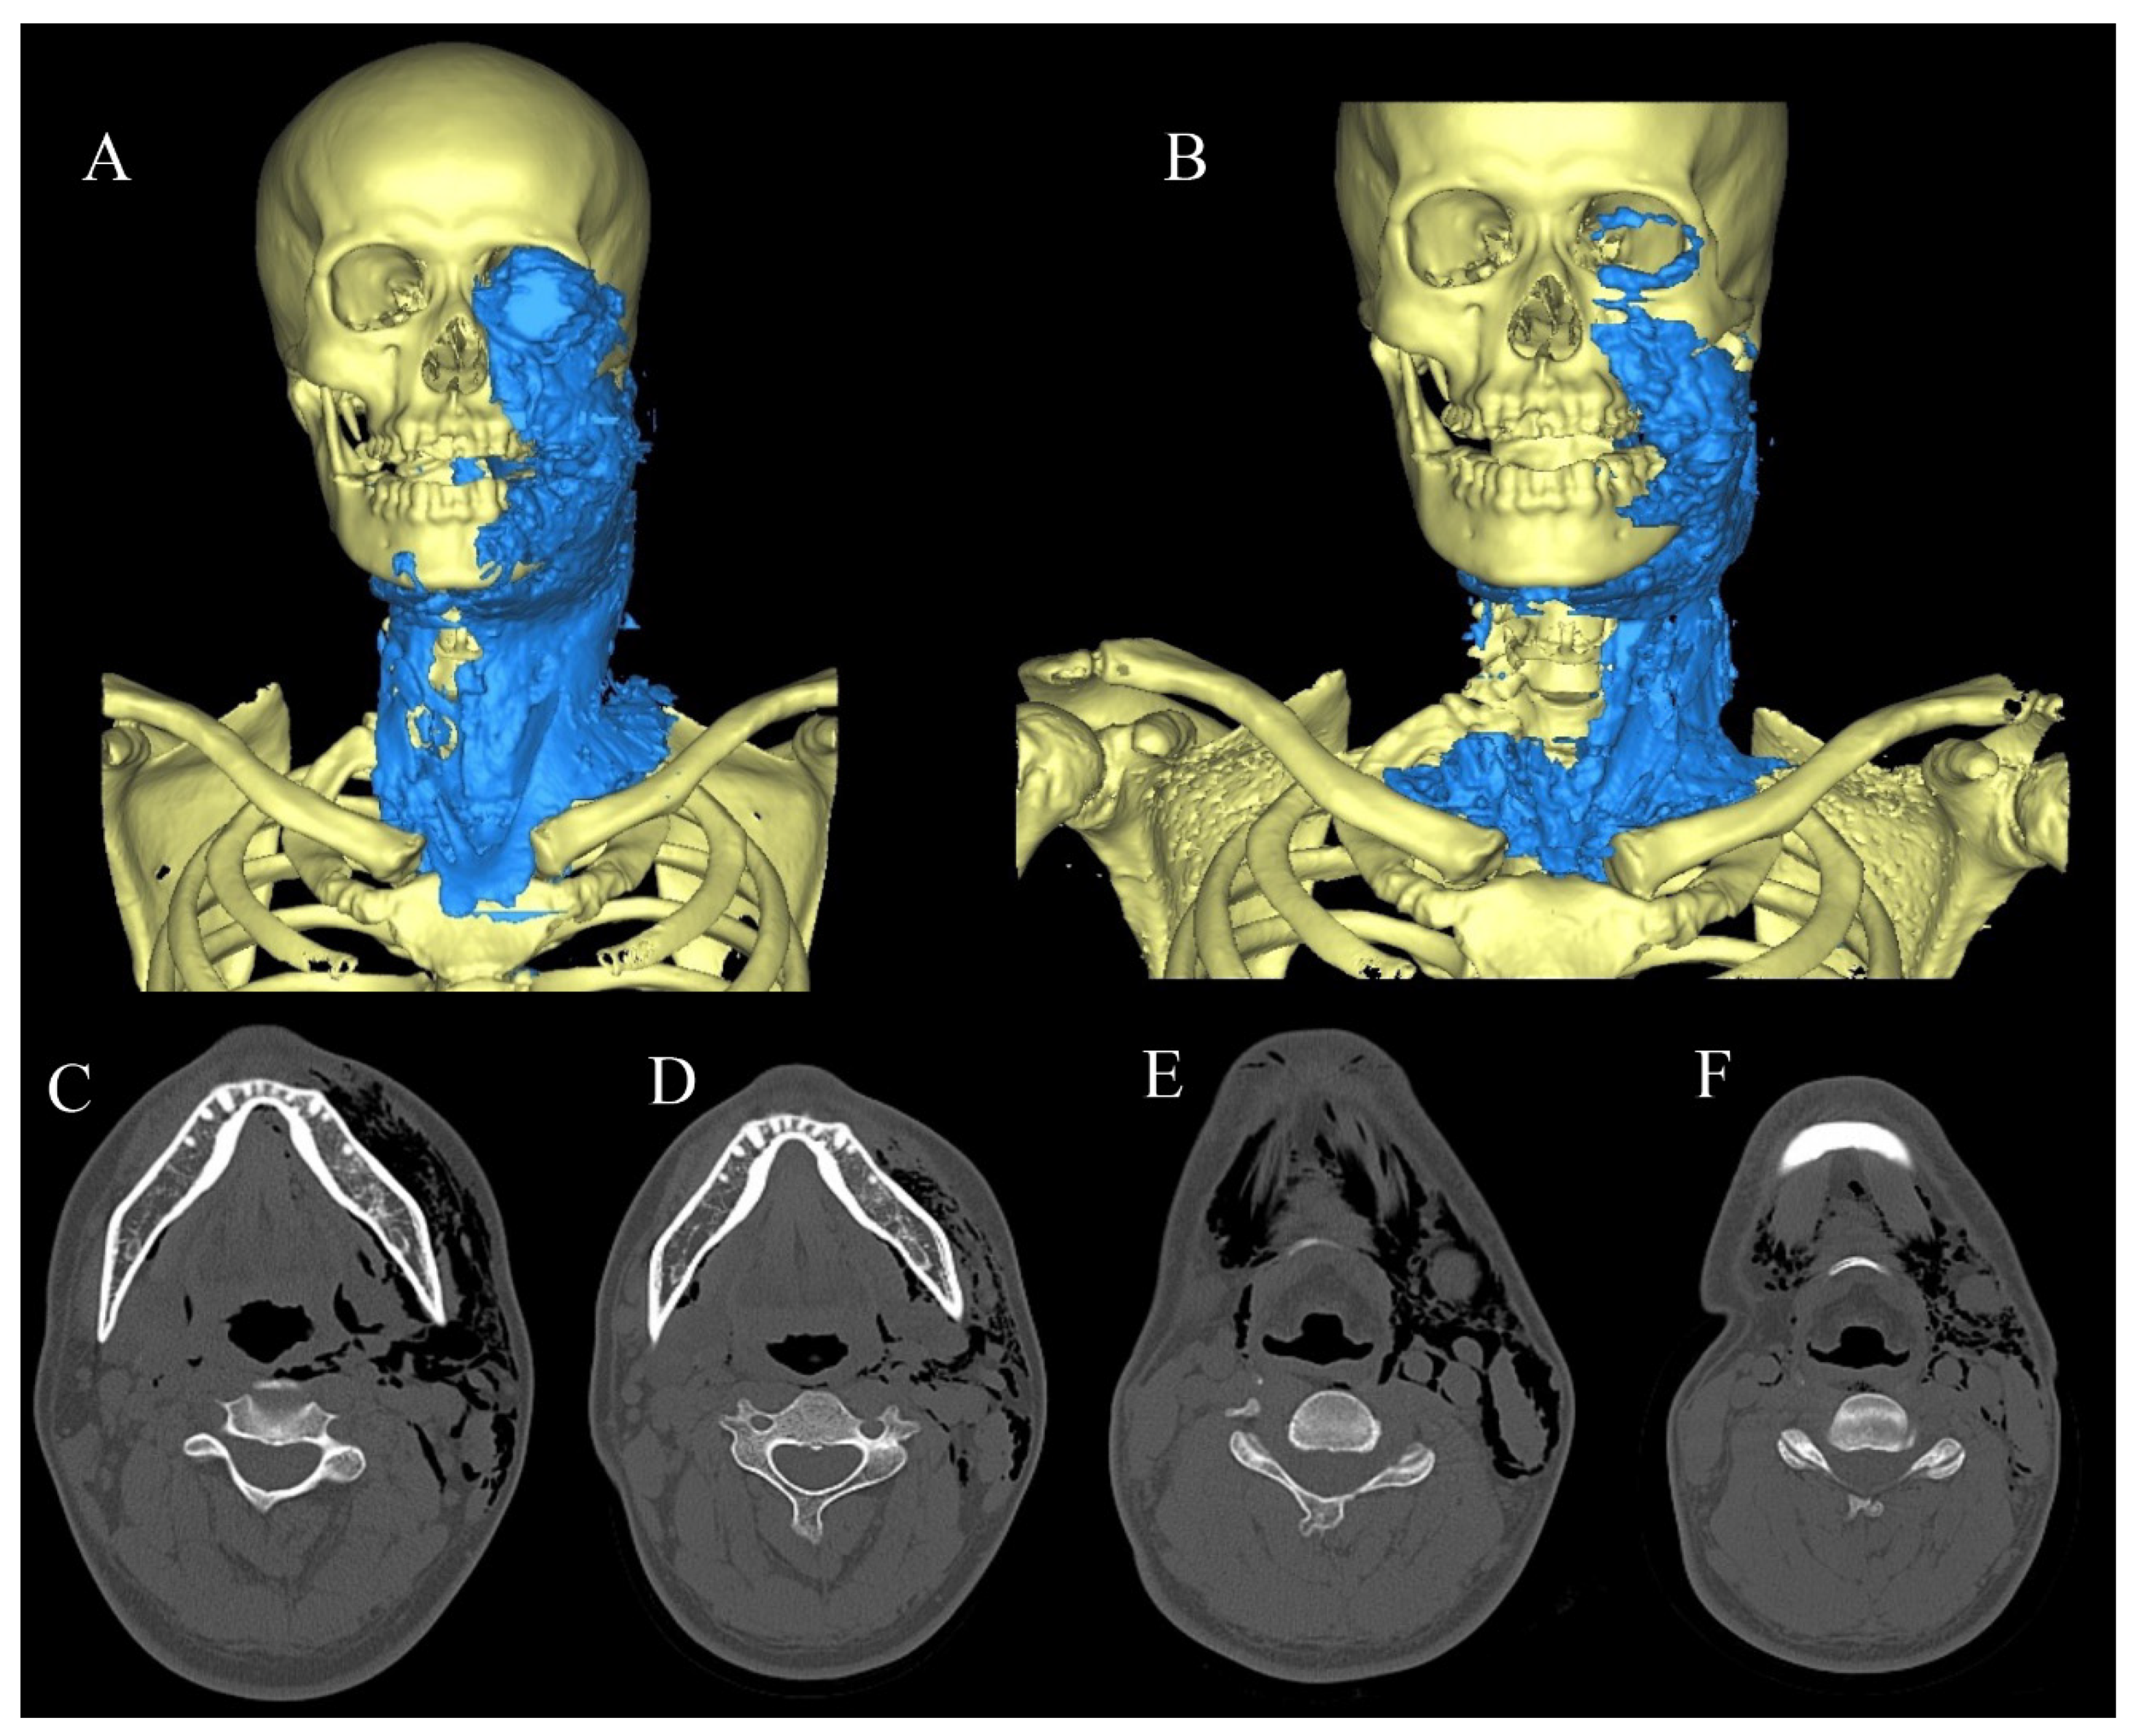

2.1. Range of Spread to Each Gap of SE

2.2. SE Volume Measurement Method

2.3.1. Case 1

2.3.2. Case 2

2.3.3. Case 3